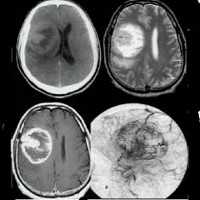

Менингиома лобной доли: КТ-картина. После введения контрастного вещества виден характерный вид «колеса со спицами» в структуре слабо контрастируемой опухоли. Несмотря на то, что данный паттерн чаще наблюдается при ангиографии, он также отмечается на томографических изображениях.

МРТ того же пациента, выполненная после предыдущей КТ: аксиальное Т1-взвешенное изображение после введения гадолиния и аксиальное Т2-взвешенное изображение. Видна крупная менингиома лобной области, расположенная срединно, со специфическим паттерном «колеса со спицами».